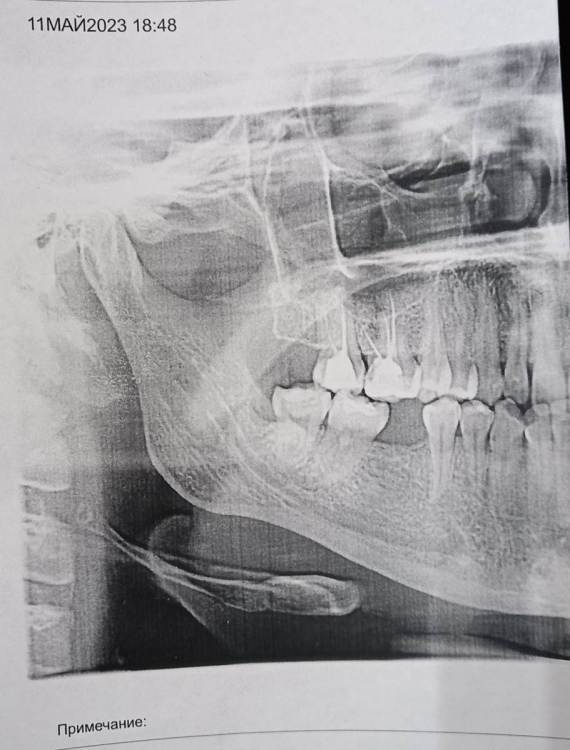

Mariaduya Опубликовано 5 июля, 2023 Поделиться Опубликовано 5 июля, 2023 (изменено) Здравствуйте. У меня сложная ситуация, боли в челюсти практически 1.5 года. Врачи не видят проблем, уже не знаю куда обратиться. Хронология. 1. В ноябре 2021 начал слегка болеть 1.6 зуб. В стоматологии мне его сразу начали депульпировать, без снимка. В ходе лечения не болел, как запломбировали каналы, постепенно появилась ноющая, постоянная боль. Я обратилась снова, сказали, что на зубе есть хроническое воспаление и ввели антибиотик туда при помощи электрофареза. Среагировал 2.5 зуб с другой стороны, и тоже начал постоянно болеть, он был депульпирован давно, но в нем развился большой кариес. 2. Мне начали их перелечивать. 1.6. не получилось пройти канал, залили резодентом, 2.5 просто переличили. 3. Боль все ещё осталась, уже в двух зубах. Врачи ничего не знают, отправили к неврологу, ЛОРУ и т.д. 4. Обошла неврологов, лоров, делала мрт, кт с контрастом головы, пазух носа, все ок. Невролог выписывает финлепсин, не помог. 5. Делала в частной клинике кт зубов, без описания, ещё не знала, что оно нужно, врач посмотрела и сказала, что видит небольшое, хроническое воспаление на 1.6 зубе и все, а так она не знает. 6. И так 1.5 года никто не знает, что со мной. Боль 1.6 и 2.5 зубы, начинают и нижние зубы болеть, уже и ухо болит. После орви болит все очень сильно, что хочется уже не просыпаться. Удалять их говорят не показаний, вдруг боль останется. Снимки в хронологии выкладываю. Есть ли на них воспаление 1.6 зуба, 2.5 зубов, есть ли них кисты свищи и все что угодно, что аномально и может вызывать боль. Может что-то с надкостницой, или суставами. Все что у меня есть - интернет, так как живу я очень далеко от нормального города и доступна только городская поликлиника, где врачи говорят, что это неврология, а невролог говорит наоборот. Сами зубы болят странно, по очереди. Если болит неделю 1.6 зуб, то 2.5 не болит и так наоборот. Вместе они не болят. Ещё странное то, что они практически симметричны друг другу по расположению. Изменено 5 июля, 2023 пользователем Mariaduya Ссылка на комментарий

Carioznik Опубликовано 5 июля, 2023 Поделиться Опубликовано 5 июля, 2023 Здравствуйте, 27 зуб надо внимательнее посмотреть, возможно там пульпит (но это неточно "бумажные " снимки малоинформативны). Скиньте лучше КТ или хотя бы ОПТГ но в электронном формате(а не фото распечатки на бумаге) Ссылка на комментарий

Mariaduya Опубликовано 8 июля, 2023 Автор Поделиться Опубликовано 8 июля, 2023 Уже после лечения 25 и 16 зубов, он отличается от современного только тем, что перелечивали ещё нижний 6 зуб. А так, такая же ситуация, как и на сегодня. Ссылка на комментарий